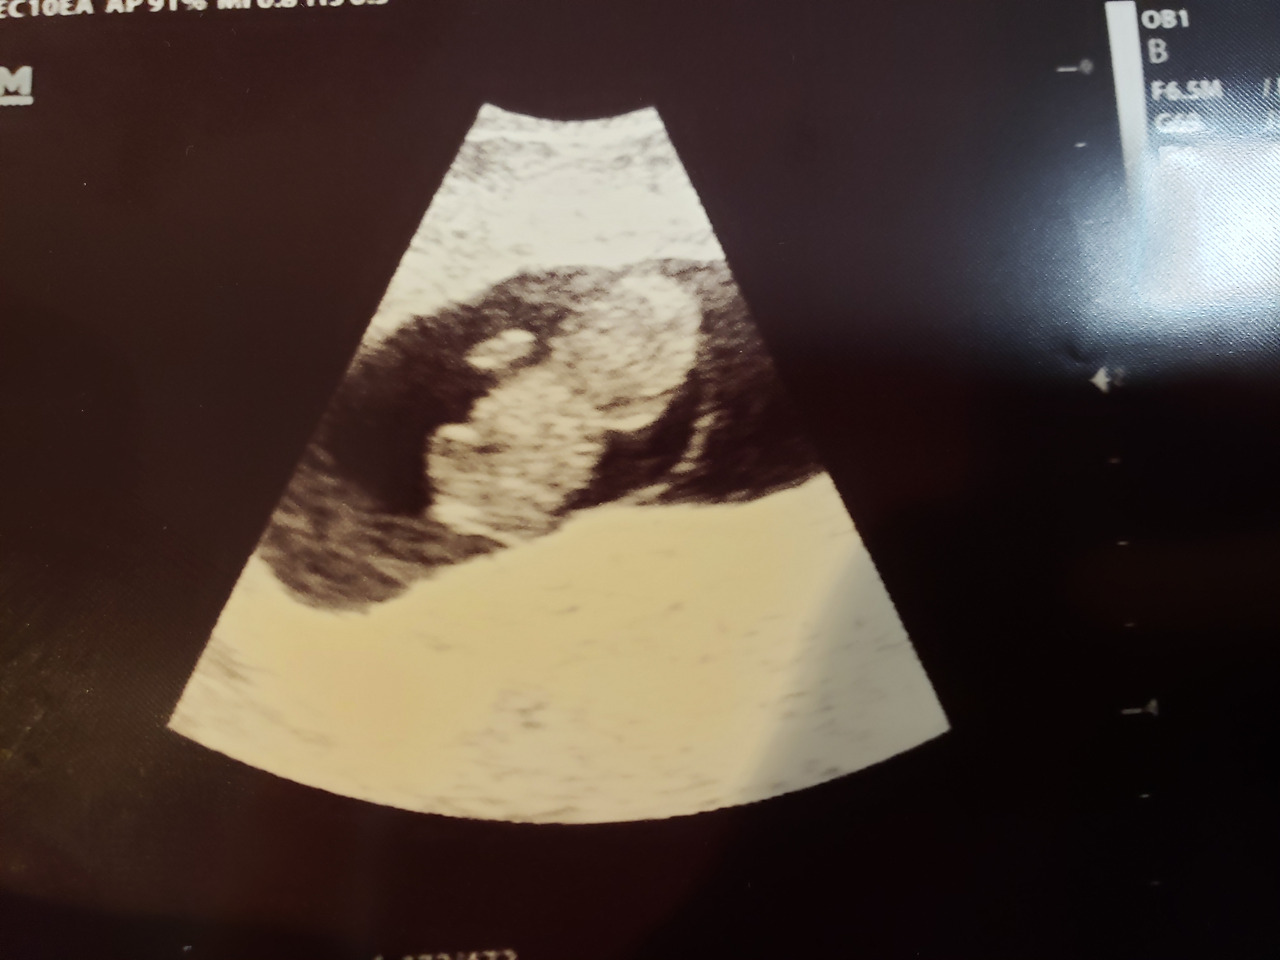

8주 3일차 사랑이.

임신 8주 5일차. 병원 첫방문이었다. 친절한 의사와 간호사 덕에 그동안 힘들었던 얘기를 했다. 의사는 평범한 임신 증상이라고 내게 말했다. 질초음파를 시작하고 젤리곰 모양의 아기가 화면에 나타났다. 내겐 또렷한 아기인데 의사의 반응이 심상치 않았다. 살아있냐는 내 질문에 아이가 이상하다고 답을 했다. 심장이 뛰지 않는다고. 8주 3일차 크기로 아이의 심장은 멈춰있었다. 눈물은 나지 않았다. 결국 이렇게 된 거구나라는 착잡한 심정이었다. 의사도 간호사도 미안하다며 나를 위로했다. 옆의 남편 조차 나를 위로했다. 순간, 축하받는 입장에서 위로받는 입장이 되어버렸다.